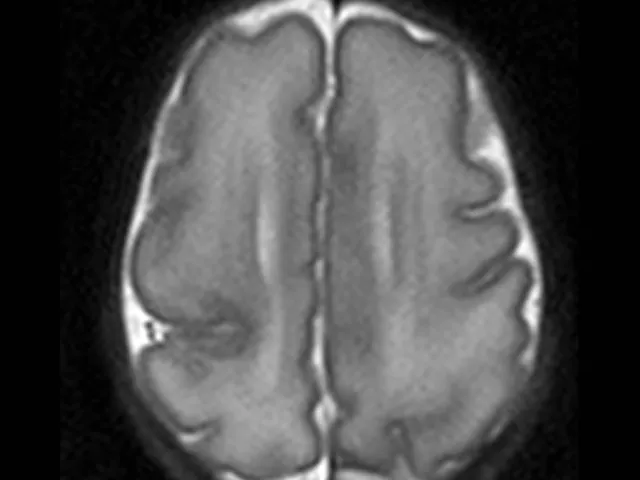

Examples of Typical MR Findings: Explore a range of typical magnetic resonance imaging (MRI) findings in patients with epilepsy. From hippocampal sclerosis and focal cortical dysplasia to more subtle abnormalities like cortical malformations, this section will highlight common and distinctive imaging features that help pinpoint the underlying cause of epilepsy.